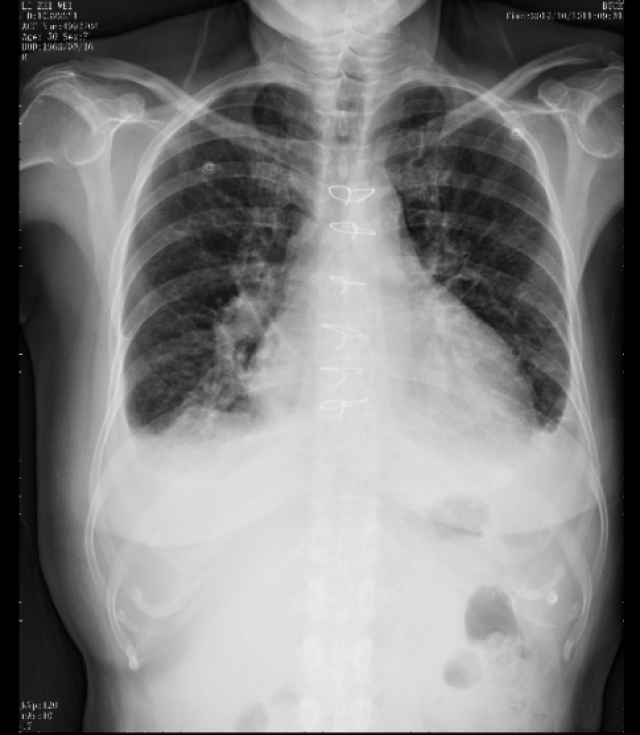

胸部X线:

双肺渗出较前明显减少,心胸比:0.53,双侧胸腔积液消失。

超声心动图:

人工瓣功能正常,左室射血分数:46%,左室舒张末径:54mm。主动脉瓣Vmax:230cm/s,二尖瓣少量反流;三尖瓣少量反流。